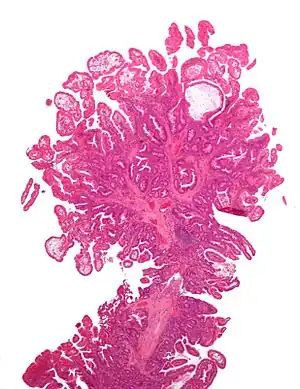

| Micrograph of Peutz-Jeghers type colonic polyp. H&E stain. | |

- Hamartomatous polyps in the gastrointestinal tract. These are benign polyps with an extraordinarily low potential for malignancy.